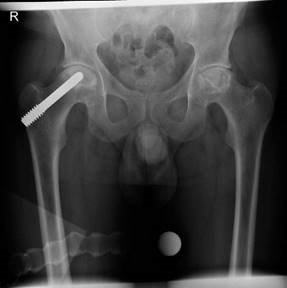

In the second method, bone marrow obtained from the pelvis is centrifuged in the operating room to yield a bone marrow concentrate rich in stem cells. The patient is supine on a traction table with a C arm image intensifier. Percutaneous core decompression drilling with a Kirschner wire (diameter 2.7 mm) is performed to perforate the interface between the necrotic lesion and healthy bone. Following this concentrated autologous bone marrow aspirate is slowly transplanted into the necrotic area under fluoroscopic control. This is still an experimental procedure but early results seem promising for early disease. EXAMINER : The patient had surgery on both hips. These are his postoperative radiographs. CANDIDATE : The AP radiograph demonstrates a metal core rod in the right hip. (Figure 2.9.) EXAMINER : What do we call this? CANDIDATE : The patient has had a tantalum rod inserted into the femoral head. The implant achieves decompression, supports the subchondral plate of the necrotic areas and probably induces bone regeneration. EXAMINER : Anything else? CANDIDATE : The use of a trabecular metal โAVN rodโ has a number of attractive theoretical advantages, including no donor site morbidity, improved rehabilitation, structural support of the femoral head and the potential for

โosseointegrationโ of the biologically friendly material. EXAMINER : The patient had core decompression performed on the left hip and a core decompression with tantalum rod inserted in the right hip. He initially got good pain relief from the procedures for about a year or so but he returns to the orthopaedic clinic complaining both hips are now painful. The left side is worse than the right. What do you think of the radiographs? CANDIDATE : The AP radiograph suggests AVN has progressed. EXAMINER : What will you do? CANDIDATE : I would offer him bilateral hip arthroplasty, the left one being more symptomatic first. EXAMINER : What type of hip replacement would you use? CANDIDATE : In view of his relatively young age I would perform an uncemented THA with a ceramic bearing surface. EXAMINER : What are the advantages of using a ceramic bearing surface? CANDIDATE : The advantages of using a ceramic bearing surface include superior lubrication, friction, and wear properties compared with other bearing surfaces in clinical use. Specifically it is an extremely hard material, very resistant to wear, with a low coefficient of friction, excellent abrasive resistance and excellent wettability properties for

Figure 2.9 Anteroposterior (AP) radiograph pelvis with tantalum rod inserted into the right hip.

Figure 2.10 Anteroposterior (AP) radiograph left metal-on-metal (MOM) hip and right ceramic large jumbo hip arthroplasty.

There is also concern of tantalum residue within the joint space found in the majority of conversions. Although there is no catastrophic wear seen in studies there is the potential for accelerated joint damage in the medium to long term. EXAMINER : These are his radiographs. He had a large jumbo head MOM performed on the left side and a large ceramic jumbo head THA performed on the right side. Do you have any worries? (Figure 2.10.) CANDIDATE : The BOA released a statement after the annual conference at Torquay in 2011 reporting a higher than anticipated early failure rate for large jumbo head MOM hips. Concern was expressed regarding the trunnion at the โMorseโ taper where the large diameter metal head attaches to the stem. Various examples were shown of damage from either wear or corrosion or both resulting in either loosening of the acetabular component, loosening of the femoral component or a metal reaction with necrosis and soft tissue damage. As such its use should now be avoided. Excluding the ASR implant theses devices have a reported revision or impending revision rate of 12โ15% at 5 years. EXAMINER : What about follow-up? CANDIDATE : This should be as per BHS guidelines for MOM bearing surfaces, yearly for the first 5 years and probably for life. Pain in this group of patients should be taken seriously and investigated appropriately with cobalt chromium levels and an MRI scan of the hip looking for any local reaction/ tissue necrosis/presence of pseudotumour. EXAMINER : What about the other ceramic hip? CANDIDATE : There are some worries again regarding the trunnion, where the large ceramic head attaches to the stem which may be the source of excessive wear or corrosion, leading again to early failure, although the evidence is not as strong. Endnotes 1. If you initially miss a subtle AVN spot diagnosis it is extremely difficult to recover the viva especially if the candidates before and after you spot it without prompting.